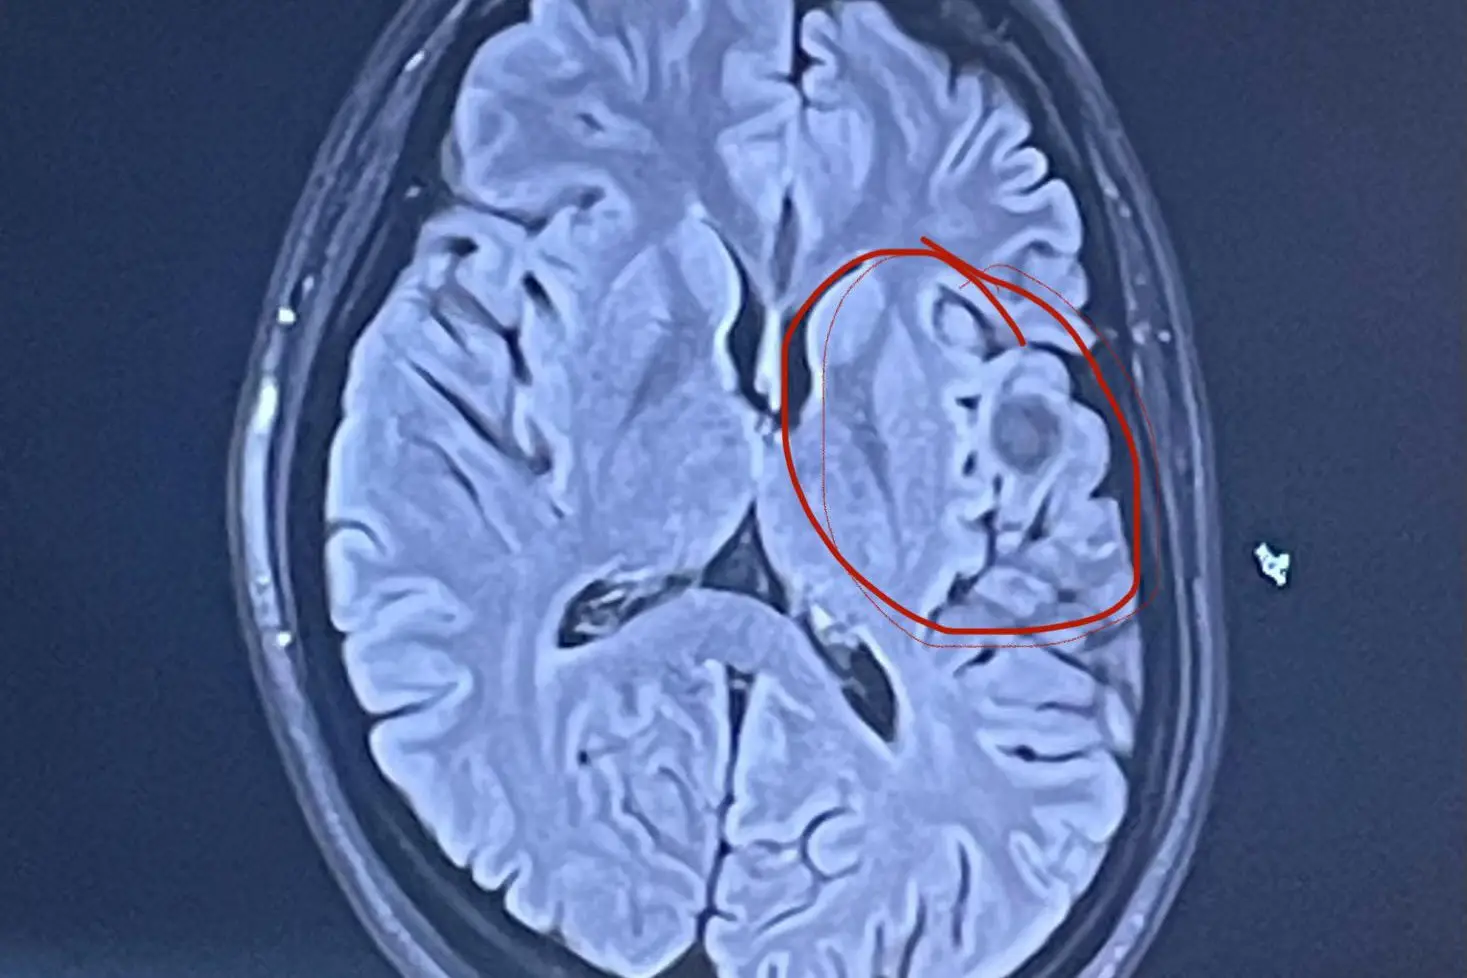

A CT scan revealed a growth the size of a golf ball on the left frontal lobe, the part of the brain that is responsible for behaviour.

Durando was eventually diagnosed with a non-cancerous cavernoma, which is a cluster of abnormal blood vessels.

Because of its location, she cannot have surgery as it could compromise her speech and behaviour, meaning every three months she has scans to monitor the growth.